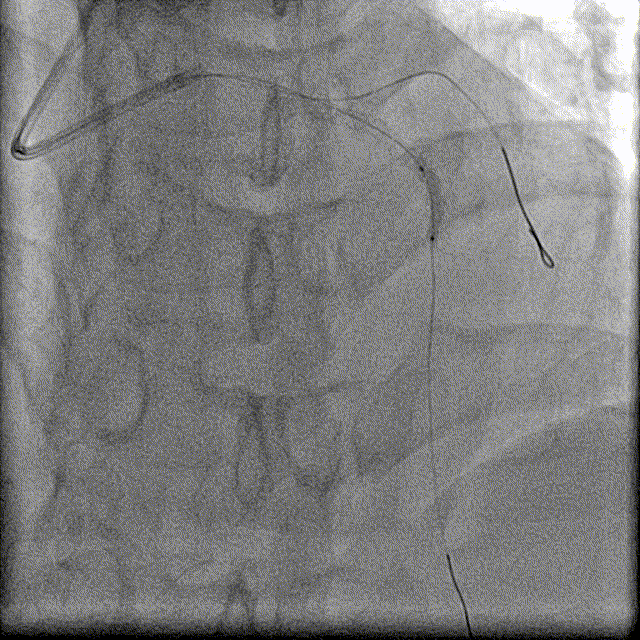

患者为冠状动脉粥样硬化性心脏病,单支病变(累及LAD);左前降支近段完全闭塞,植入支架后有再狭窄;左前降支近段介入治疗(扩张球囊);CTO病变使用正向导丝技术开通。

右冠脉造影

左冠脉造影

导丝微导管通过

交换导丝后造影

球囊扩张支架

IVUS证实在LAD真腔内,多次球囊扩张近中段闭塞处,但是前向血流始终无法恢复,提示左室壁室壁瘤形成后,无有效存活心肌。

介入治疗最后造影

再次介入术后最后造影

左室造影